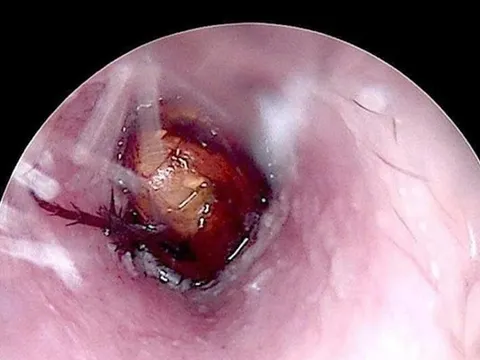

Điều trị nhiều lần ở châu Âu không khỏi, nam bệnh nhân bay từ Hà Lan sang Việt Nam để phẫu thuật nội soi 0

Người đàn ông Hà Lan bị khàn tiếng hơn một năm, điều trị nhiều lần ở châu Âu không khỏi, vừa phục hồi sau phẫu thuật Laser CO₂ tại một bệnh viện của Việt Nam.